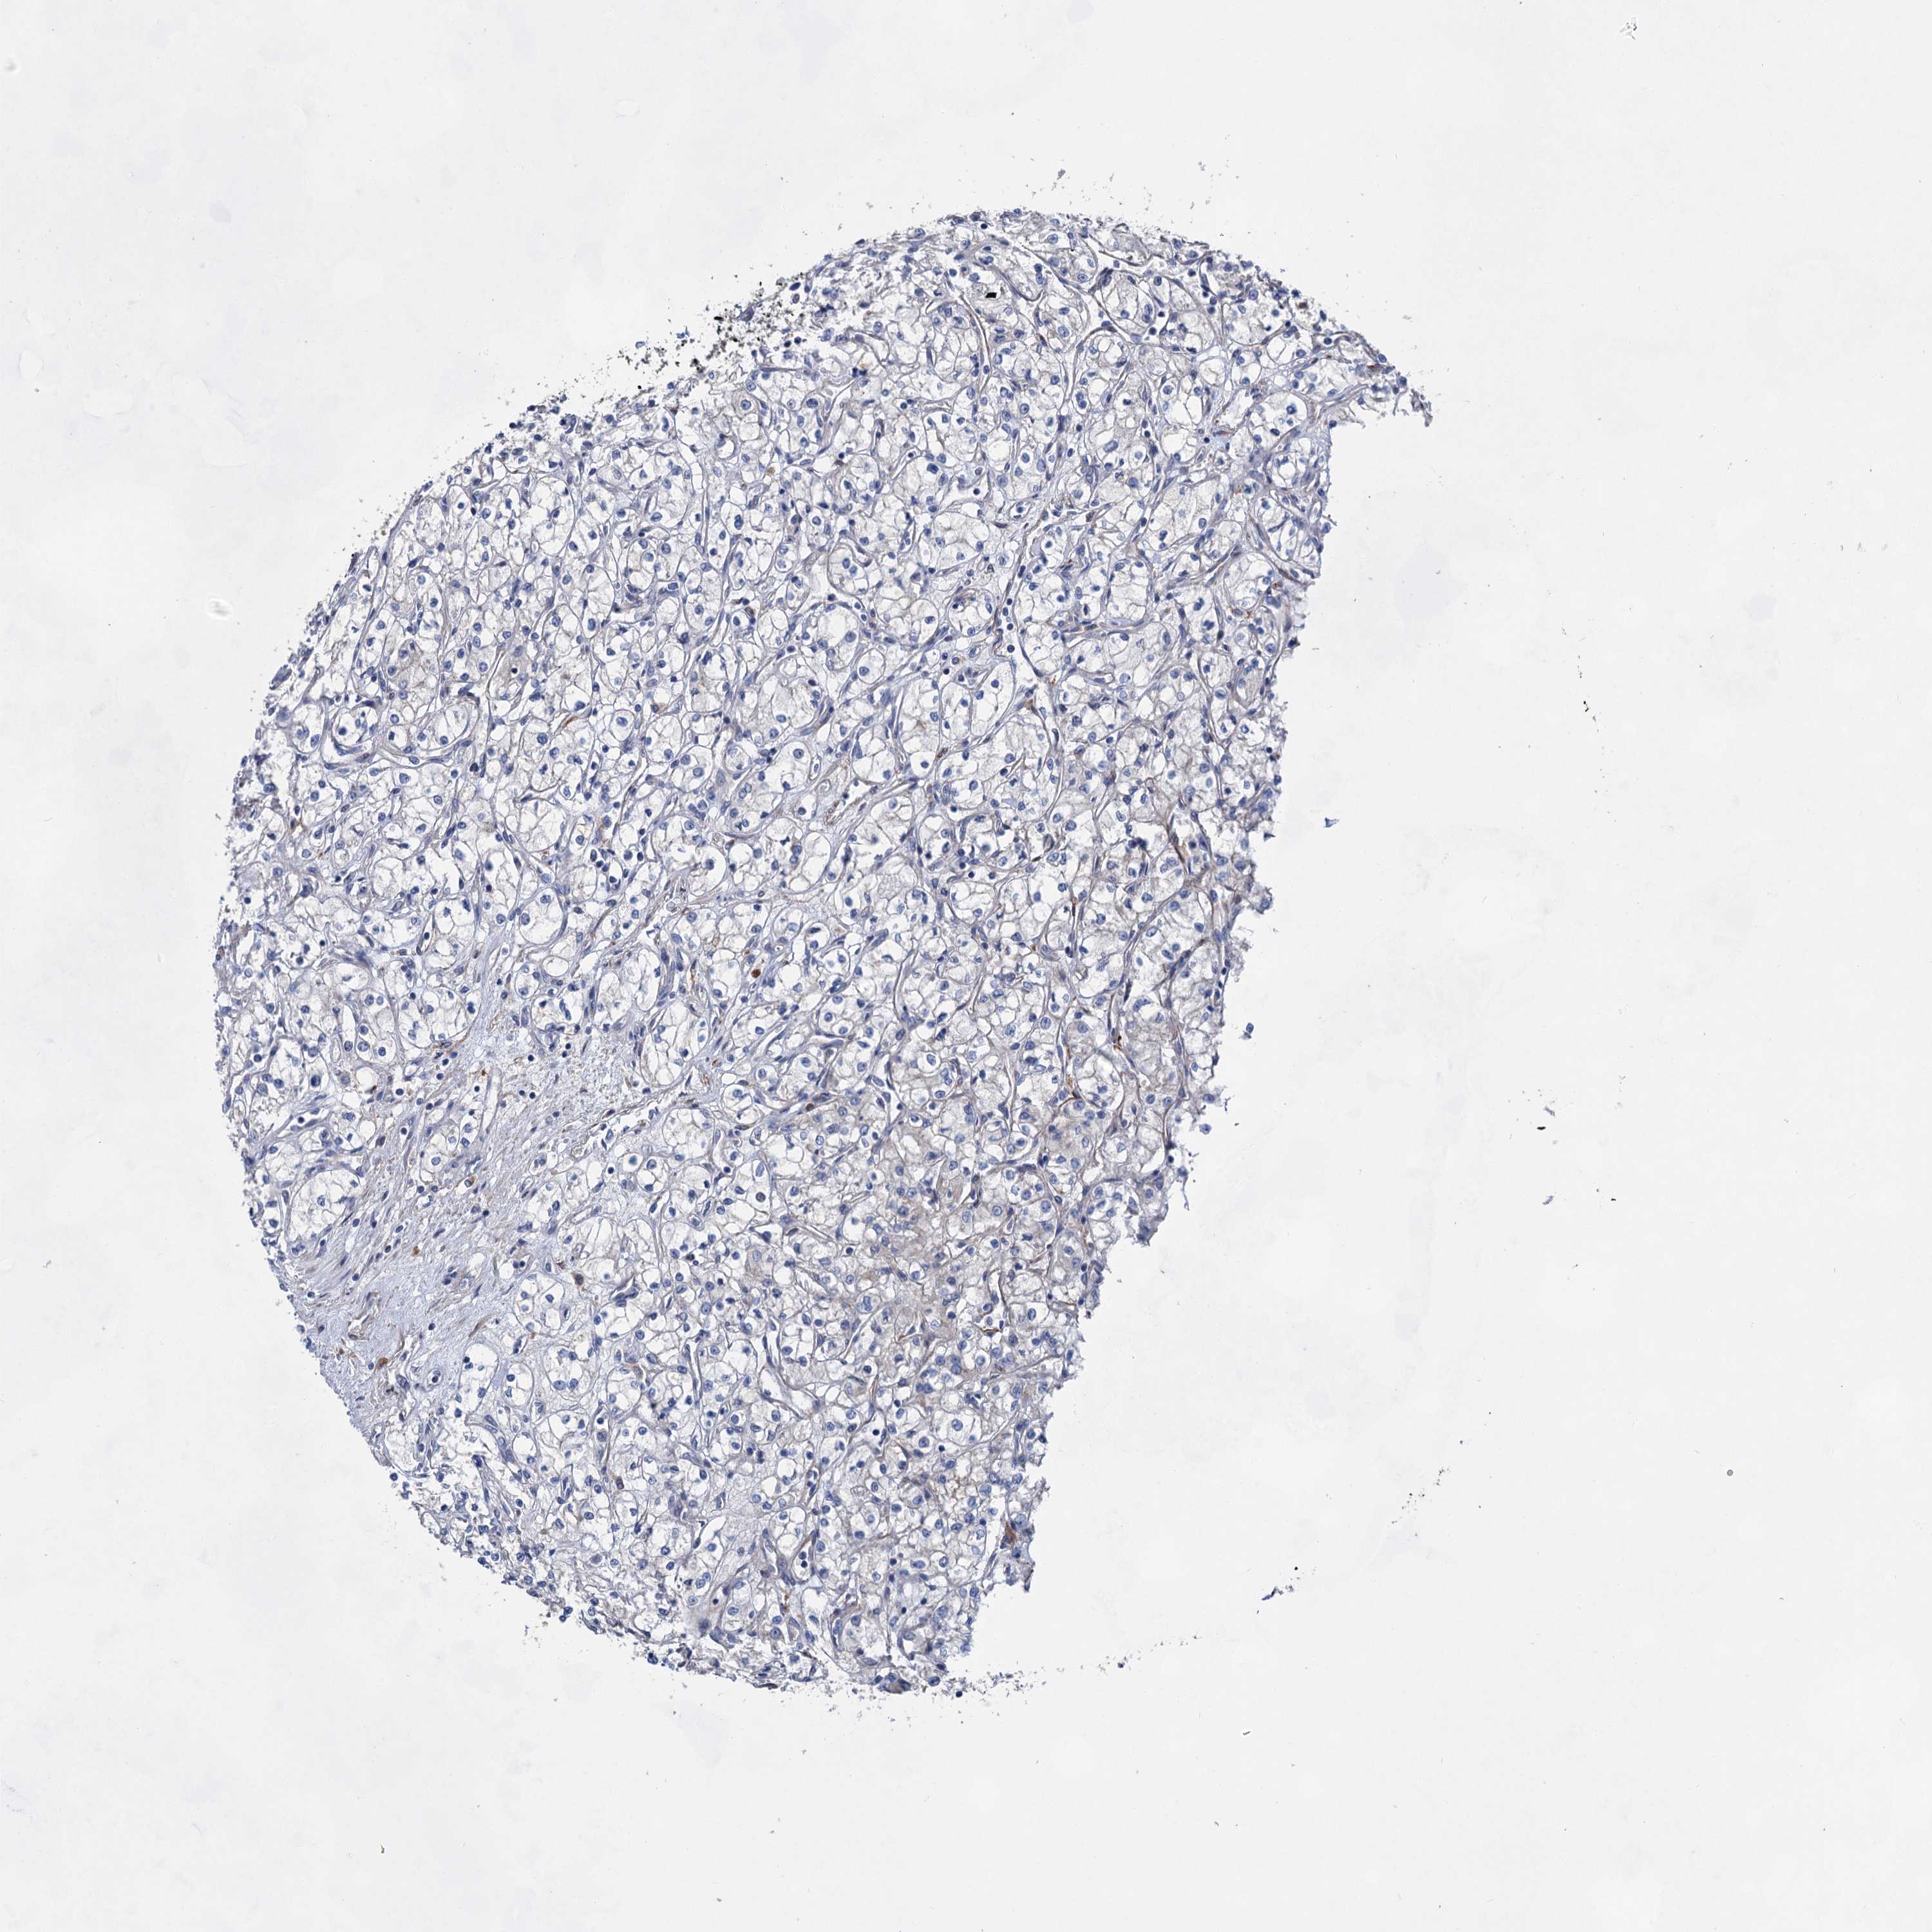

CANCER RENAL CANCER Show tissue menu

KICH TCGA KIRC TCGA KIRC VALIDATION KIRP TCGA PROTEIN RCC CPTAC PROTEIN EXPRESSION